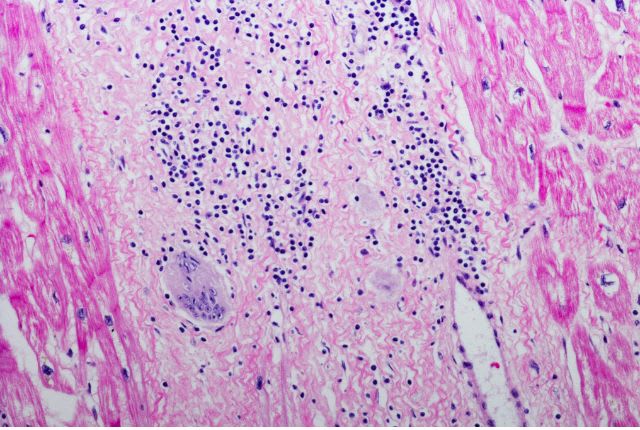

Pour diagnostiquer une sarcoïdose, les médecins s’appuient généralement sur deux facteurs : une augmentation du volume des ganglions lymphatiques et des résultats anormaux à la tomodensitométrie (TDM) ou à la radiographie du thorax. Pour confirmer le diagnostic, une biopsie est nécessaire pour mettre en avant la présence de granulomes. Pour cela, un prélèvement de tissu est réalisé sur un organe atteint (peau, poumon, ganglions entre les poumons, rein, etc.). Un bilan complet est nécessaire, c’est pourquoi d’autres examens sont généralement menés, tels qu’une radiographie pulmonaire, un examen du souffle (exploration fonctionnelle respiratoire) et un scanner thoracique lorsque la sarcoïdose touche les poumons. En cas d’atteinte cardiaque, un électrocardiogramme et une échographie cardiaque peuvent être nécessaires. Des analyses d’urines, des examens ophtalmologiques, des analyses de sang ou encore une IRM pourront venir compléter le diagnostic selon les organes atteints.